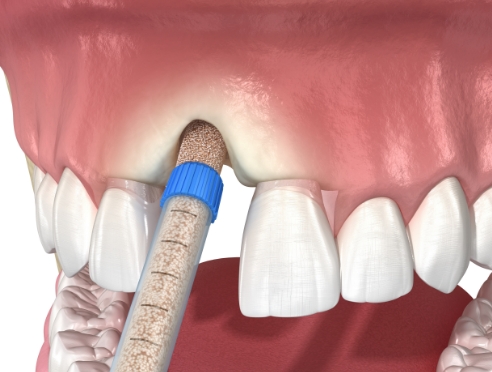

뼈 상태·신경 위치 등을 고려해

식립 위치와 시술 계획을 세웁니다.

환자 상태에 맞는 개인 맞춤

임플란트 디자인을 적용합니다.

계획된 가이드에 따라 안정적으로

임플란트를 식립합니다.